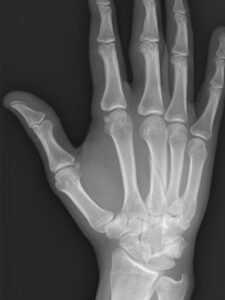

See below the two treatment approaches for a patient who has metacarpal fracture.

Fig 1: Basic Treatment

An off-the-shelf splint is being used to treat a metacarpal fracture. It does not hold the metacarpal in a stable position leading to possible complications.